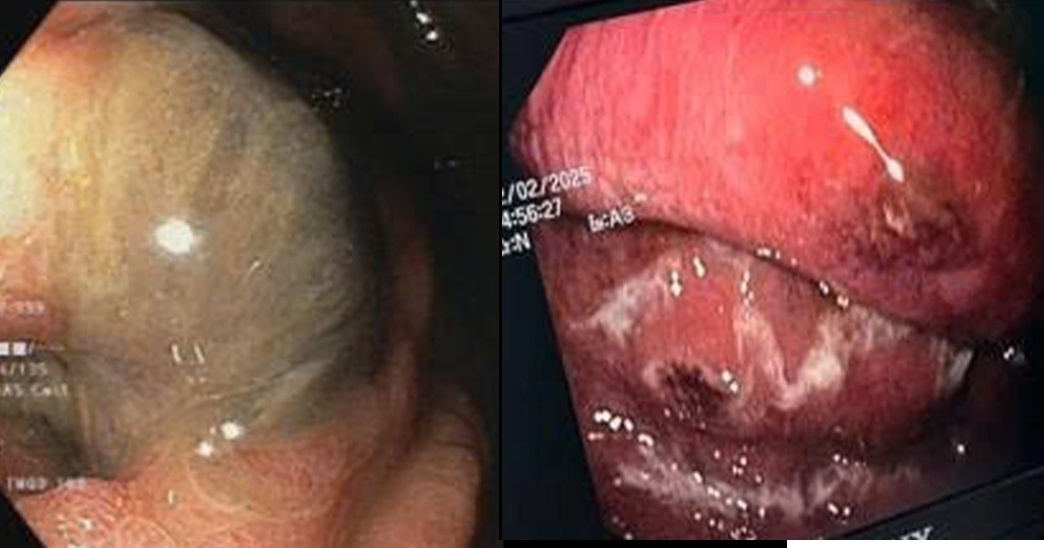

Kết quả chụp cắt lớp vi tính ổ bụng và nội soi dạ dày - thực quản cho thấy phần lớn thành thực quản và dạ dày bị viêm, phù nề và hoại tử sinh hơi; niêm mạc xung huyết, mủn nát. Các bác sĩ xác định đây là tình trạng viêm hoại tử sinh hơi dạ dày - thực quản (Emphysematous Esophagogastritis) - thể bệnh hiếm gặp và có tiên lượng rất nặng.

Hình ảnh niêm mạc dạ dày thực quản xung huyết, mủn nát và có lỗ thoát mủ. Ảnh: BVCC.

Theo thạc sĩ, bác sĩ Nguyễn Sỹ Thấu, khoa Hồi sức Truyền nhiễm (A4-D), kết quả cấy máu phát hiện vi khuẩn Streptococcus constellatus. Đây là loại vi khuẩn thường trú ở niêm mạc đường tiêu hóa nhưng gần đây được ghi nhận có thể xâm nhập và gây viêm hoại tử tại nhiều cơ quan.